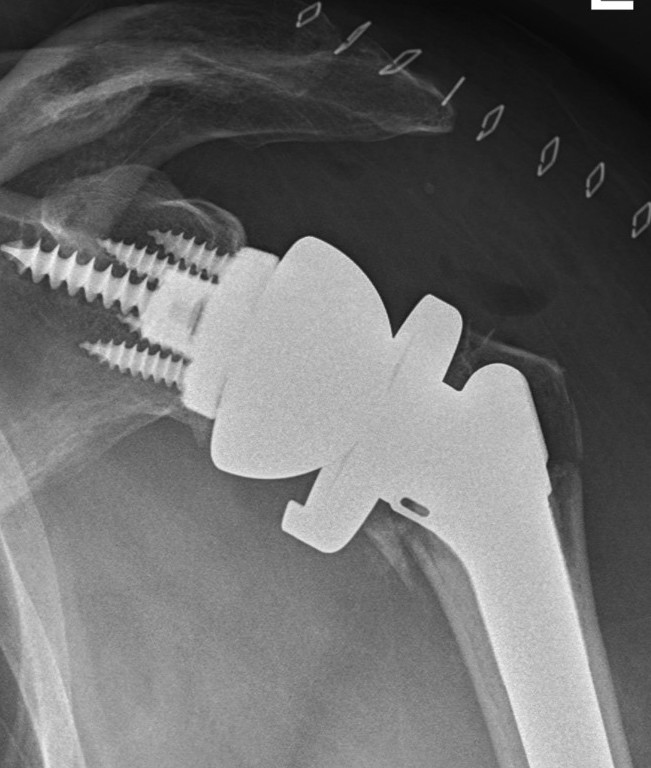

Reverse total shoulder arthroplasty

Indications

Unreconstructable fracture in elderly > 65

- comminuted, 3 or 4 part

- head spltting fracture

- off ended / 100% displaced

Technique

Cemented versus uncemented

Kao et al Eur J Orthop Traumatol 2023

- systematic review of 34 studies cemented v uncemented rTSA for proximal humerus #

- improved Constant score with cemented rTSA

- no difference in complications

Rossi et al JSES 2022

- systematic review of 45 studies cemented v uncemented rTSA for proximal humerus #

- no difference in outcomes

- high complication rate uncemented rTSA 10% v cemented 6%

Tuberosity fixation / healing

Vaccaro et al JSES 2025

- rTSA for proximal humerus #

- improved functional outcomes with tuberosity healing

O'Sullivan et al JSES 2020

- systematic review of 800 patients with rTSA for fracture

- improved forward flexion and abduction with tuberosity healing